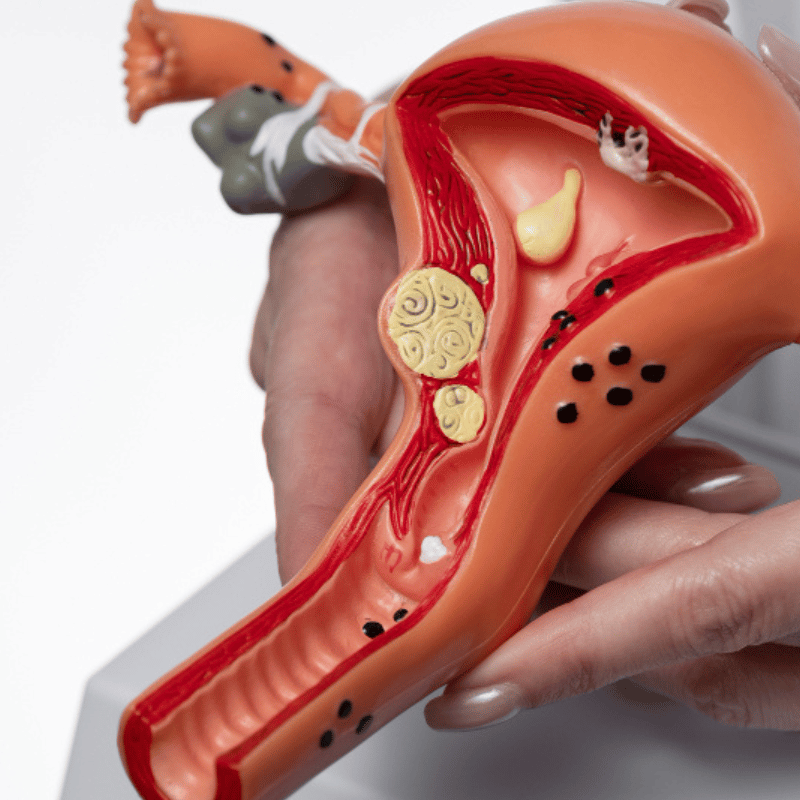

PCOS

Fibroids

Endometriosis

Adenomyosis

Ovarian Cyst